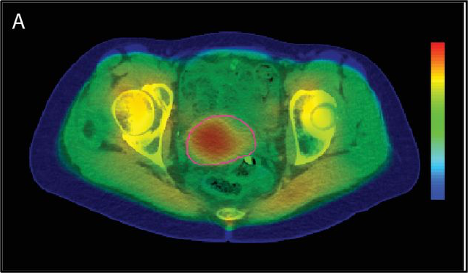

תזרים העבודה למתן טיפול בהיפרתרמיה מקומית-אזורית (locoregional) כולל מספר שלבים. ראשית, היפרתרמיה צריכה להיות מתוכננת ברצף עם מתן הקרנות. באופן כללי, היפרתרמיה ניתנת פעם בשבוע זמן קצר לפני או אחרי פרקציות ההקרנות. במקרים חריגים מסוימים, היפרתרמיה ניתנת פעמיים בשבוע, עם לפחות 3 ימים בין כל מפגש כדי למנוע אינדוקציה של עמידות תרמית. כדי להשיג את התועלת המרבית של היפרתרמיה כרדיוסנסטיזטור, מרווח הזמן בין הקרנות להיפרתרמיה צריך להיות פחות משעה אחת. במרכז של החוקרים, לאחר מיקום של צנתרים פולשניים מינימליים להחדרת בדיקות טמפרטורה בנרתיק, בשלפוחית השתן ובפי הטבעת, נעשה CT תכנון היפרתרמיה (hyperthermia planning CT) של המטופלת על מזרן ההיפרתרמיה ובולוס המים מסביב עם צנתרי הבדיקה התרמית האלה במקומם (איור 2A). CT זה משמש לחלוקה אוטומטית של רקמות בעלי תכולת מים גבוהה לעומת אלו עם תכולת מים נמוכה עבור תכנון טיפול בהיפרתרמיה, כאשר הגידול מותאם על ידי הרופא, בהנחיית ה-MRI שנעשה לתכנון הקרנות (איור 2B). בנוסף, ה-CT משמש לקביעת אילו מנקודות מדידת הטמפרטורה מייצגות גידול ואילו רקמה נורמלית לבקרת טמפרטורה אופטימלית במהלך הטיפול. מטרת תכנון הטיפול בהיפרתרמיה היא לקבוע את הגדרות המכשיר האופטימליות וכתוצאה מכך חימום טוב של הגידול תוך הימנעות מחימום יתר של רקמות רגילות (איור 2A).

להלן איור A2: תכנון טיפול היפרתרמיה כאשר הגידול בצוואר הרחם מתואר באדום בסריקת CT היפרתרמיה ייעודית עם בדיקות תרמיות במקום שנעשו ישירות לפני טיפול ההיפרתרמיה. מוצגות גם הנקודות החמות (האזור האדום) והקרות (האזור הירוק).

להלן איור B2: סריקת MRI כסיוע לקווי מתאר המתאימים של הגידול ב-CT